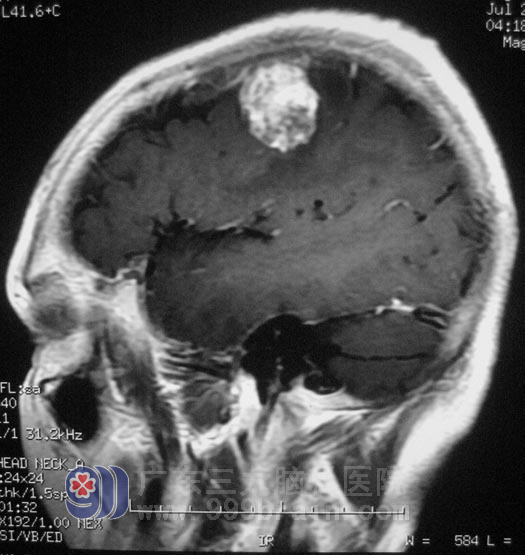

好心的邻居提醒她:“去做个检查看看,有病早治疗,没病就权当为自己做个体检”。在当地医院行MR检查,结果提示:左侧额顶叶占位,医生考虑脑膜瘤可能,建议手术治疗。http://www.999brain.com/

家里人选择了广东三九脑科医院,综合神经外科 鲁明主任也考虑脑膜瘤可能性大。

8月18日,由鲁明主任主刀,在全麻下行左侧额顶部占位切除术,术中见灰红色的肿瘤组织,肿瘤质软,前方与中央沟引流静脉粘连紧密,其余方向边界清,沿血管壁、肿瘤与脑组织分界处仔细分离肿瘤,肿瘤达辛普森I级切除。术后经过治疗,兰姨自诉右侧手掌部、足背部痛温觉较术前好转,不再有蚂蚁爬行的感觉。经病理证实为:(左额顶部)皮细胞型脑膜瘤,WHO I级。